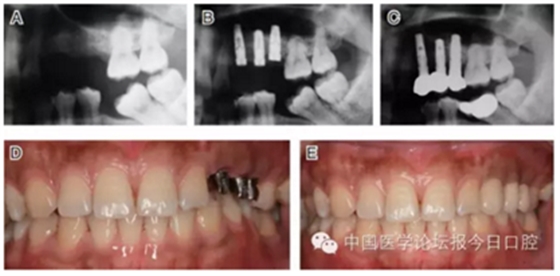

病例8 多顆種植體植入(圖10)

圖10